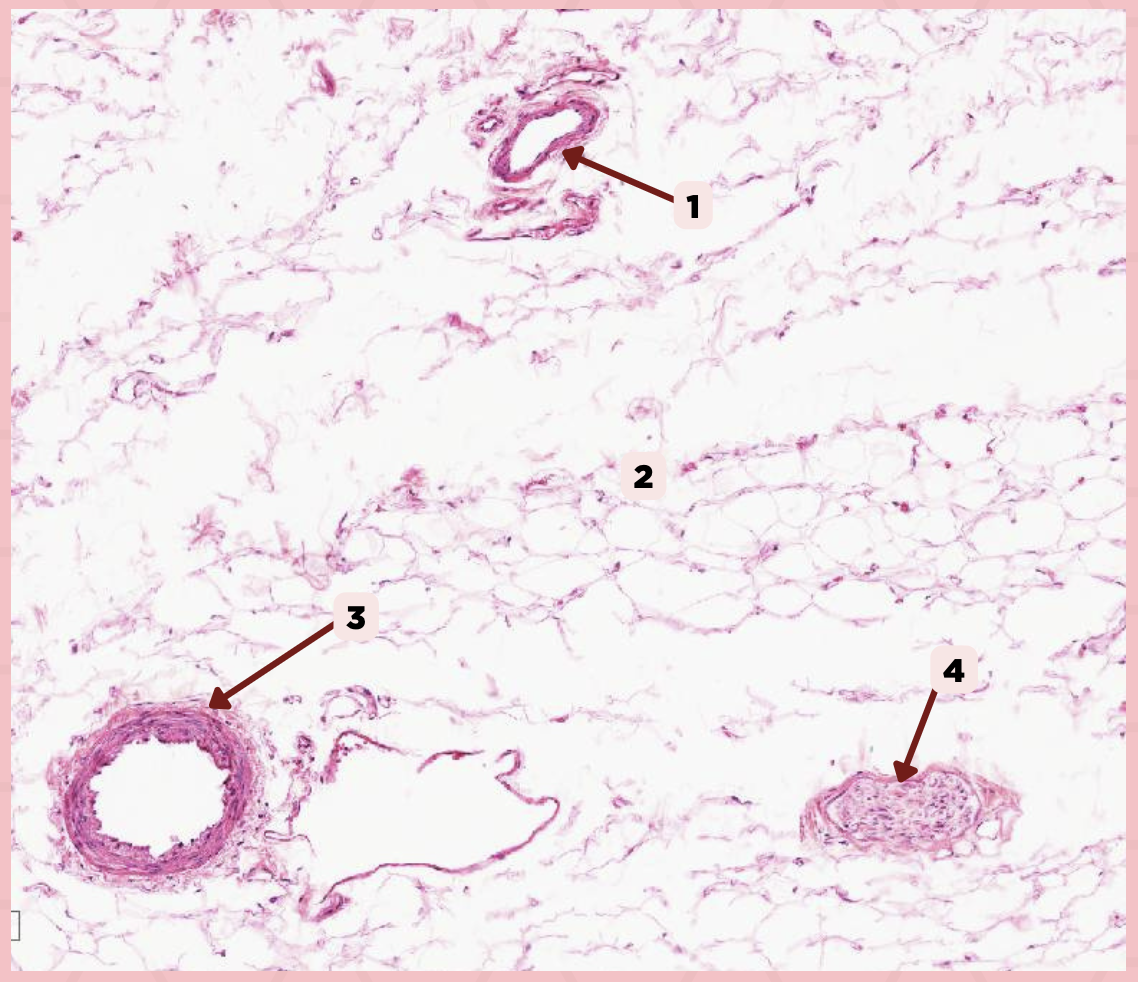

Cheek

Identify the specimen.

Vein

Identify the structure labeled as 1.

Hypodermis

Identify the structure labeled as 2.

Artery

Identify the structure labeled as 3.

Nerve

Identify the structure labeled as 4.